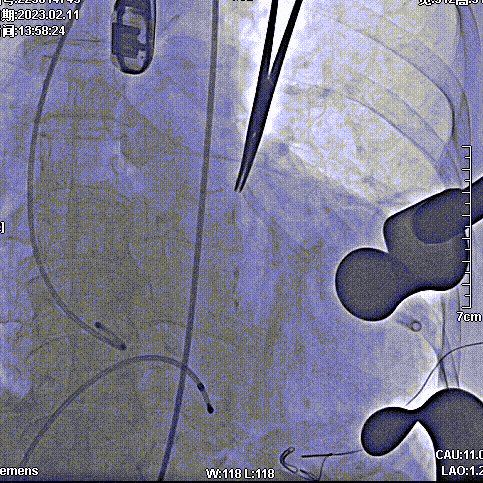

2月11日,新疆维吾尔自治区人民医院杨毅宁教授团队成功应用J-Valve完成两例具有挑战性的横位心TAVR病例。其中一例为窦部扩张+横位心,另外一例为升主动脉增宽+横位心,且两例患者均为主动脉瓣关闭不全(反流)。

病例一:窦部扩张与横位心

病史简介:71岁女性,因心慌、胸闷、气短4月入院。

手术步骤